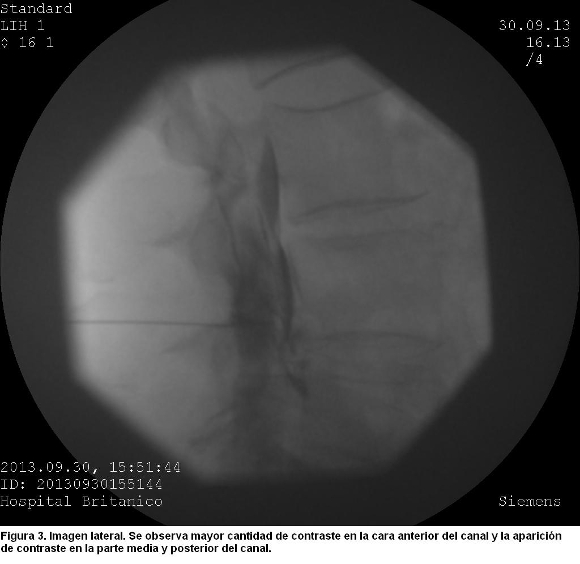

Al inyectar más contraste en tiempo real, luego de retirar unos milímetros la aguja con la intensión de obtener una imagen periradicular, se observó en visión lateral una mayor concentración del contraste en la parte anterior del canal, una opacidad en la parte media del canal, y una línea de contraste sobre la parte dorsal del canal espinal (figura 3).